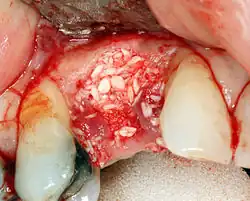

Rekonstrukce tvrdých tkání (kosti)

Kostní štěp je nutný při nedostatku kosti. Také pomáhá stabilizovat implantát tím, že zvyšuje jeho přežití a snižuje okrajový úbytek úrovně kosti.[37] I když stále existují nové typy implantátů, například krátké implantáty, a techniky umožňující kompromis, obecným cílem léčby je minimální výška kosti 10 mm a šířka 6 mm. Případně jsou defekty kosti odstupňovány od A do D (A=10+ mm kosti, B=7–9 mm, C=4–6 mm a D=0–3 mm), přičemž pravděpodobnost oseointegrace implantátu souvisí se třídou kosti.[38]:s.250

K dosažení odpovídající šířky a výšky kosti byly vyvinuty různé techniky kostních štěpů. Nejčastěji se používá tzv. metoda řízené augmentace kostním štěpem, kdy se defekt vyplní buď přirozenou (odebranou nebo autotransplantovanou) kostí, nebo alotransplantátem (kost dárce nebo syntetická kostní náhrada), překryje se polopropustnou membránou a nechá se zahojit. Během fáze hojení přirozená kost nahradí štěp a vytvoří nový kostní základ pro implantát.[34]:s.223

Tři běžné postupy jsou:[38]:s.236.

- Sinus lift

- Laterální alveolární augmentace (zvětšení šířky místa)

- Vertikální alveolární augmentace (zvětšení výšky místa)